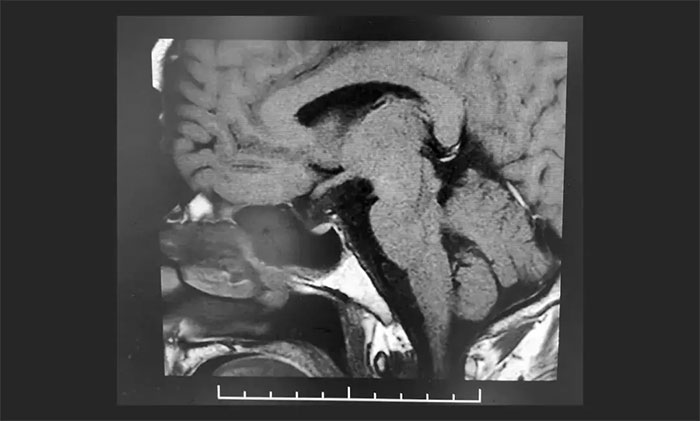

▲ 術(shù)后影像顯示腫瘤被切除